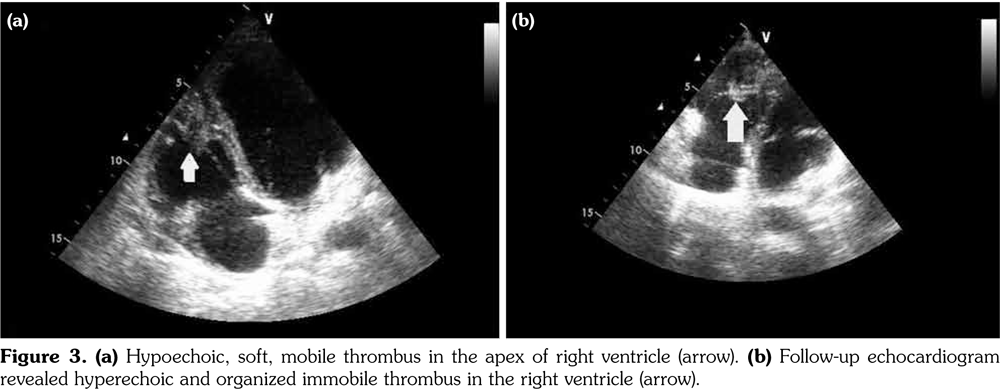

Chest X-ray showed left parahilar opacity (Figure 1). Pulmonary computed tomography (CT) angiogram revealed PAA with thrombus (Figure 2a). Bronchoscopy revealed no origin of bleeding. Echocardiography demonstrated mobile thrombus in the right ventricle (Figure 3a). Blood and urine cultures were sterile. Venereal Disease Research Laboratory test, tuberculosis tests, human immunodeficiency virus serology, antiphospholipid antibodies, anti-nuclear antibodies, and anti-neutrophil cytoplasmic antibodies were negative. Hereditary coagulation thrombophilic factors were normal.

The patient was treated with pulse steroid (intravenous methyl prednisolon 1 g/d for three days), intravenous cyclophosphamide (1 mg/kg/d), peroral azathioprine (125 mg/d) and peroral colchicine 0.5 mg/d. Peroral prednison was given after intravenous methyl prednisolon. Anticoagulation therapy was not administered. Patient was followed-up to one year. Reevaluation with pulmonary CT angiograms and echocardiograms demonstrated a remarkable regression of PAAs, and organization of intracardiac thrombus (Figures 2b and 3b, respectively). Currently, the patient is in a stable condition without hemoptysis or embolic event.